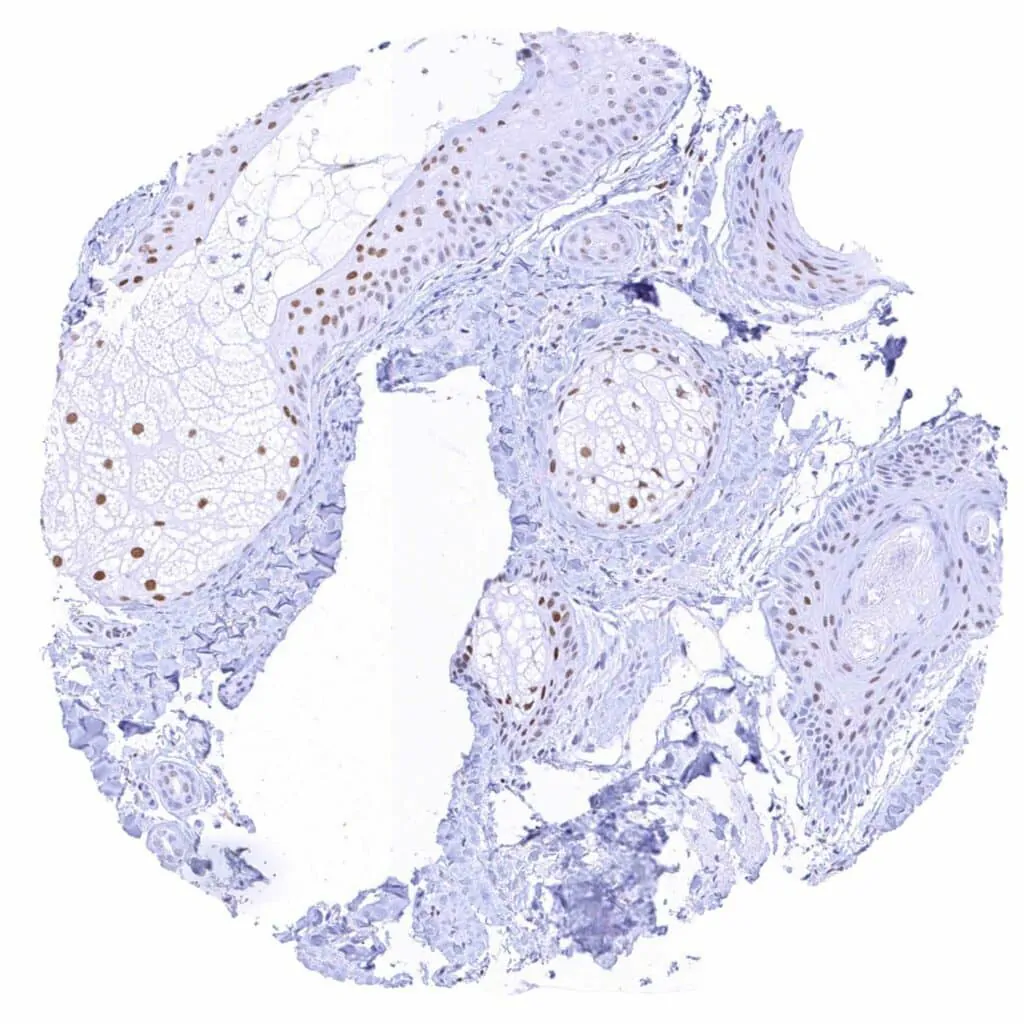

Skin, hair follicel and sebaceous glands – Moderate to strong TLE1 positivity of sebaceous and of squamous cells